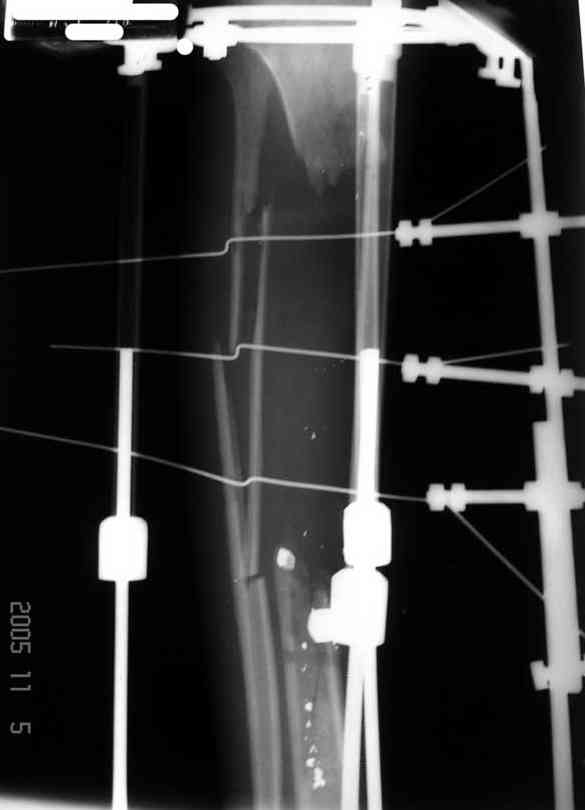

Re: case tibial defect

Я думал, что в нижнем отделе голени без мягкотканнего покрытия будет сложно проведения тибиализацию, но твой пример показывает - метод работает даже в таких трудных условиях.

Кстати, как метод использования малоберцовой при дефектах на более высоком отделе большеберцовой, недавно с моим партнерем опубликовали в главе по замещению дефектов в книжке Роберта Росбруха и Светланы Илизаровой по Наружным Фиксаторам.

Правда те мои случаи были сделаны давно, еще в Латинской Америке, и конечно качество исполнения отстает от идеалов, но, несмотря на отсутствие нормальных спиц с упором, метод сработал в свое время.